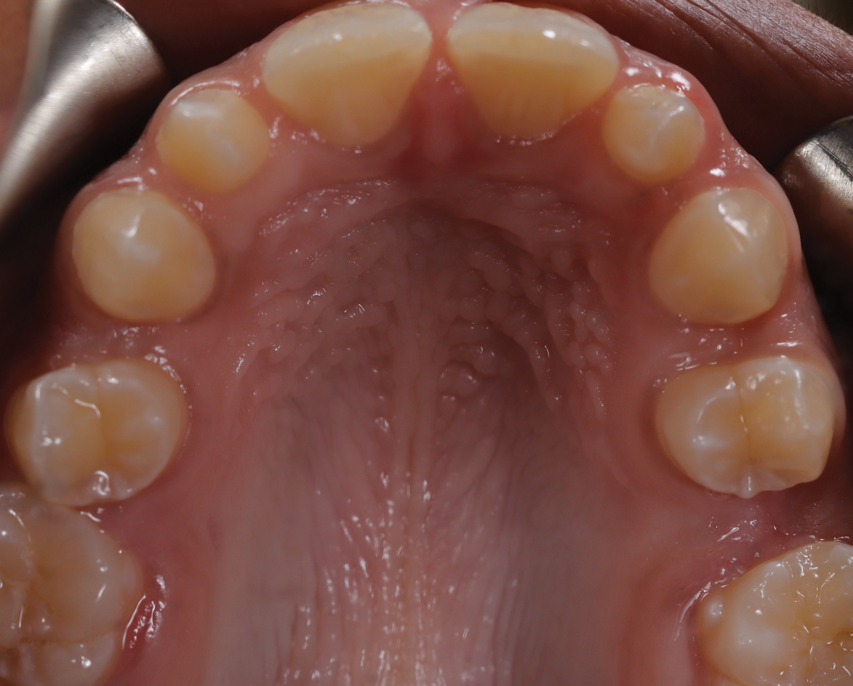

A 16-year-old female patient presented with the chief complaint that she was dissatisfied with the appearance of her anomalous maxillary lateral incisors (teeth Nos. 7 and 10) and multiple diastemas (Figure 1 through Figure 4). She had been referred for restorative treatment after an initial consultation with the orthodontist. Her first restorative appointment was dedicated to data collection, which included a health history and physical examination as well as the acquisition of photographs (facial, dentofacial, dental), videos (chief complaint, F sound, S sound), vinyl polysiloxane (VPS) impressions, a panoramic radiograph, a bite registration, and a facebow registration. The clinical examination revealed that both of the patient's maxillary lateral incisors were peg-shaped. After a discussion about the risks and benefits of different treatment options, such as direct composite restoration, indirect composite veneers, and porcelain laminate veneers, she chose to have her maxillary lateral incisors treated with direct composite buildup restorations. The index cutback technique was chosen for this case instead of a freehand technique in order to create a new shape according to an ideal wax-up but also to be able to control the thickness of the enamel layer.7

(1.) Pretreatment smile, left lateral smile, and right lateral smile photographs, respectively, showing the patient’s peg-shaped lateral incisors.

Figure 1

(2.) Pretreatment smile, left lateral smile, and right lateral smile photographs, respectively, showing the patient’s peg-shaped lateral incisors.

Figure 2

(3.) Pretreatment smile, left lateral smile, and right lateral smile photographs, respectively, showing the patient’s peg-shaped lateral incisors.

Figure 3